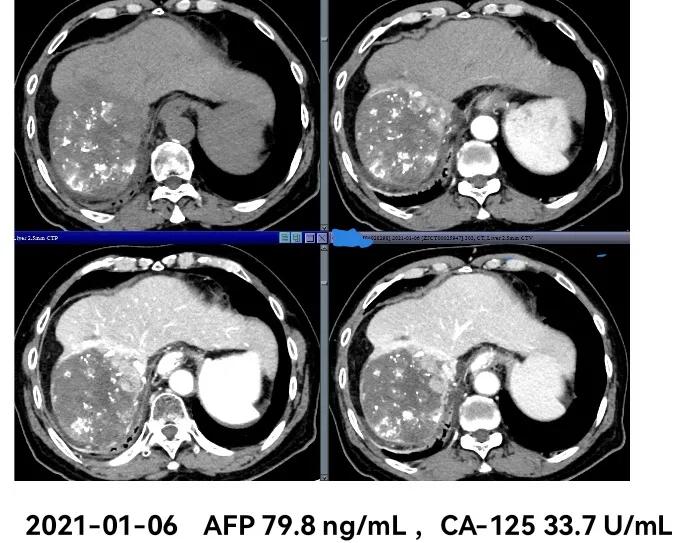

影像学检查:

治疗过程中肿瘤标记物甲胎蛋白(AFP)的变化